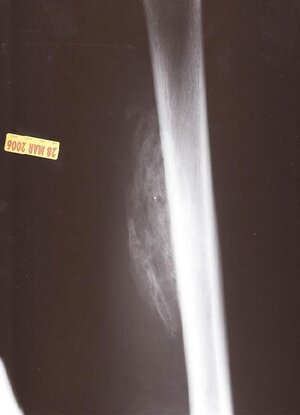

here's what yamaslut was talking about. The MRI was taken shortly after it happened. The quad muscle was shredded by the ridplate landing on it. The X-ray was taken about 4 months afterwards. It's rare but my body thought my femur was broken and turned all the surrounding muscle into bone, so I have a big lump in my leg. 6 months of physical therapy and now I'm stronger then ever. Which is nice cuz I thought I was gonna be crippled for life.